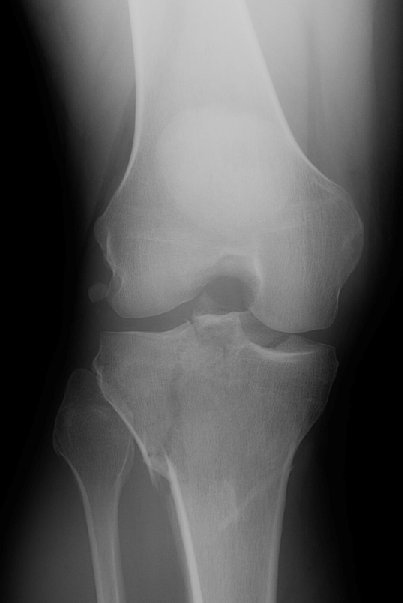

Return to Tibial Plateau Fracture